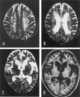

Binswanger's disease, also known as subcortical leukoencephalopathy and subcortical arteriosclerotic encephalopathy (SAE), is a form of small vessel vascular dementia caused by damage to the white brain matter. White matter atrophy can be caused by many circumstances including chronic hypertension as well as old age. [Source: Wikipedia ]